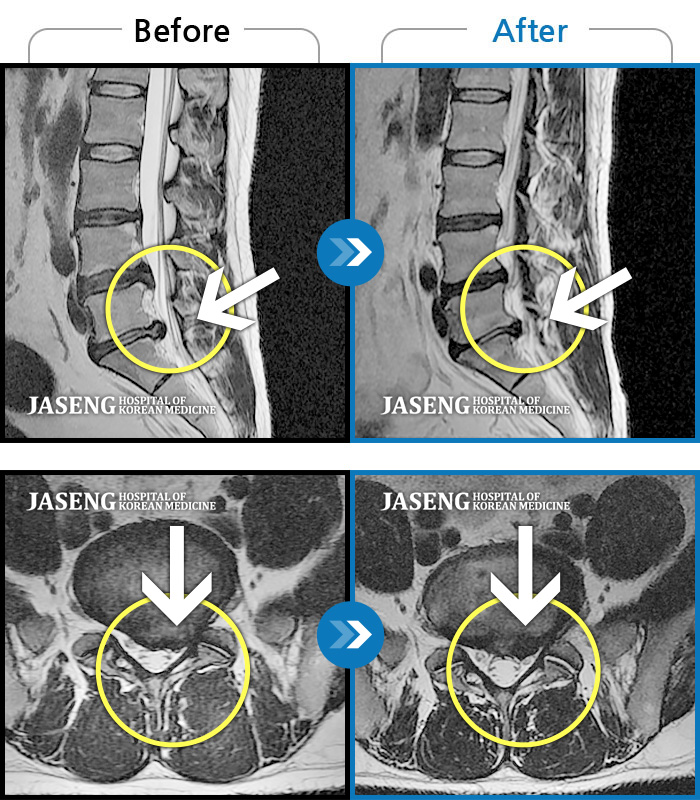

25년 1월 허리통증이 시작되고 잠을 잘수도없고 걸을 수 없을만큼의 상태가 되었을때 다시 김태용 원장님께 진료를 받고 예전 허리수술의(4번5번)(3번4번)디스크탈출증 재발과 협착증의 진단을 받고 지금까지 기나긴 여정의 입원 치료를 하며 곧 퇴원을 앞두고 있습니다.